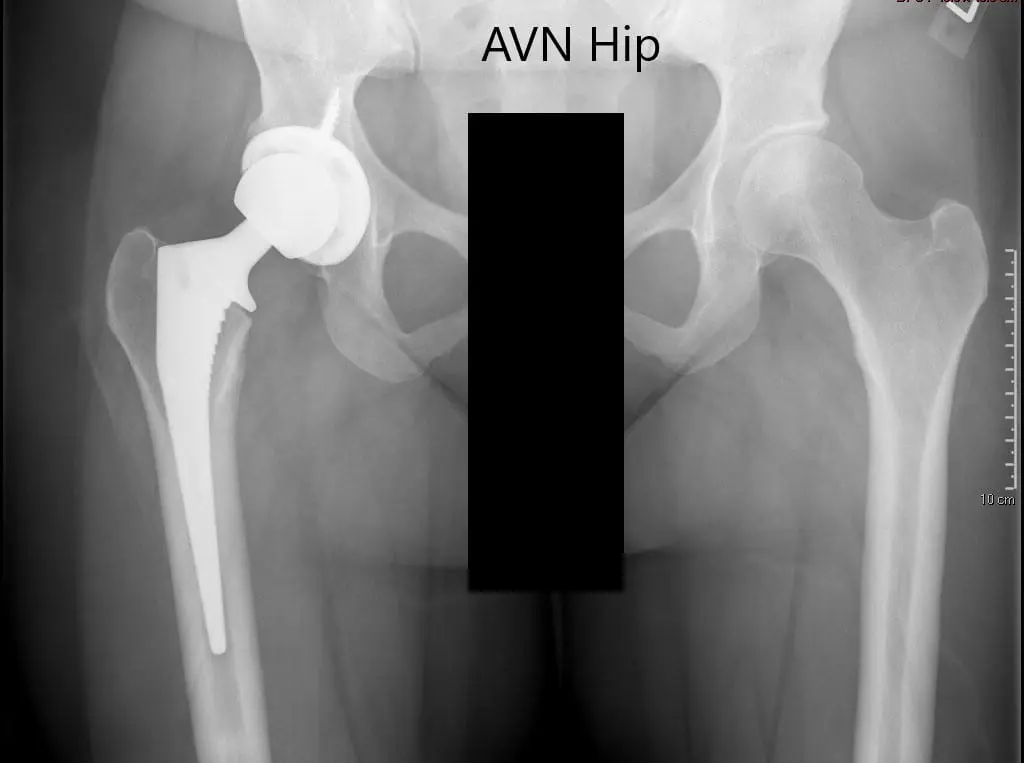

An X-ray was obtained which suggested a normal artificial joint on the right side. The left hip suggested some sclerosis with an intact spherical head of the femur. There was no crescent sign or any collapse.

Preoperative X-ray of the pelvis with both hips showing intact artificial joint on the right side and AVN of the left hip.